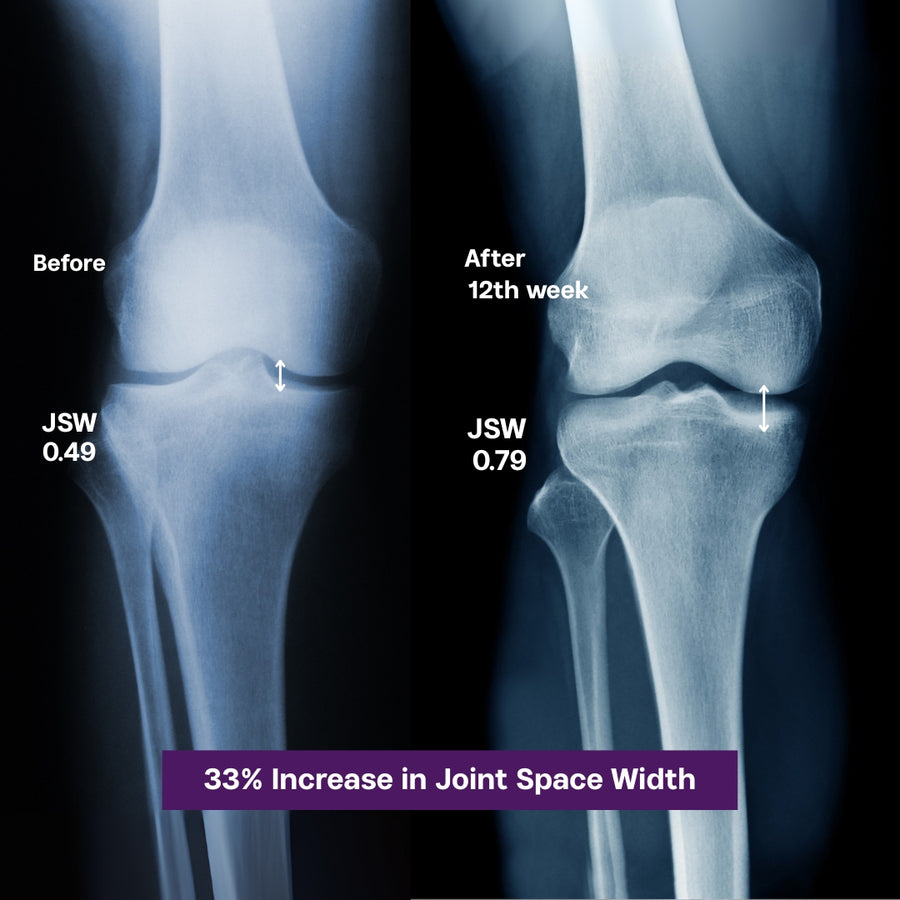

61% Increase in Joint Space Width

Proven Cartilage Support with URAH Cream in Just 12 Weeks

(From 0.49 to 0.79mm medial JSW –  which is an indirect measure of cartilage thickness)

Growing Distance Between the Two Bones (Joint Space Width - JSW): The study did find that massaging Urah (glucosamine cream) through CFM significantly increased the medial joint space width (JSW), which is an indirect measure of cartilage thickness. it shows that the mean medial JSW for the CFM group increased from 0.49 (baseline) to 0.79 (12th week).